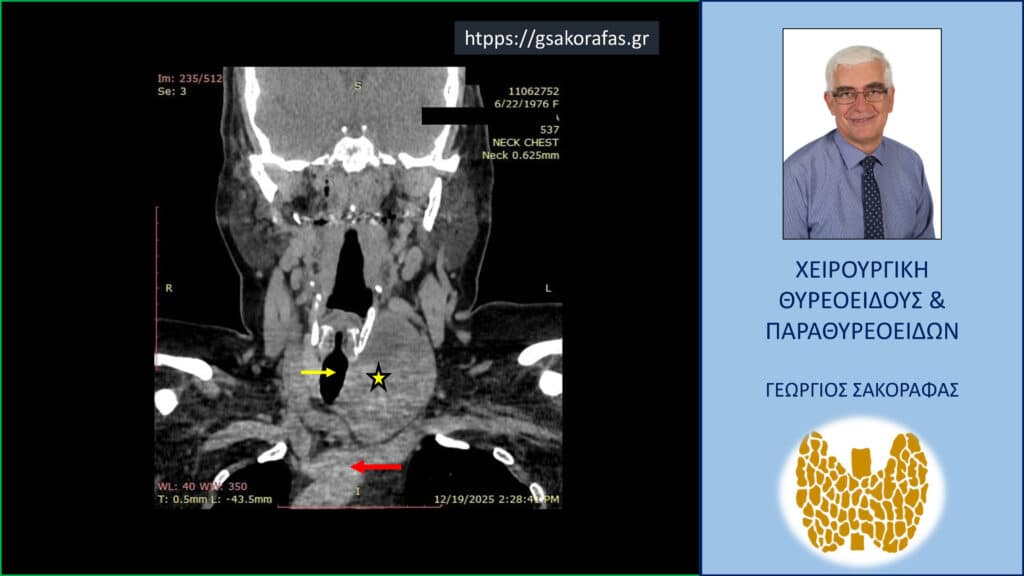

- Γιατί είμαστε σε θέση να εκτελέσουμε με ασφάλεια και αποτελεσματικότητα κάθε είδους χειρουργική επέμβαση θυρεοειδούς – παραθυρεοειδών, ακόμη και σε επιπλεγμένα (δύσκολα) περιστατικά, όπως εκτεταμένοι λεμφαδενικοί καθαρισμοί σε καρκίνο θυρεοειδούς, επεμβάσεις σε λίαν ευμεγέθεις καταδυόμενες στο μεσοθωράκιο βρογχοκήλες, υποτροπές παθήσεων θυρεοειδούς (συμπεριλαμβανομένου του καρκίνου θυρεοειδούς), υποτροπές υπερπαραθυρεοειδισμού, αδενώματα παραθυρεοειδών σε έκτοπη θέση ή λόγω υπεράριθμων παραθυρεοειδών, διάχυτη υπερπλασία παραθυρεοειδών, κλπ.